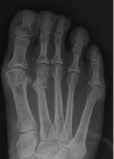

Footballers tend to have many metatarsal injuries, usually fractures such as Jones and/or March fractures. The ‘Jones’ fracture is a transverse fracture of the proximal metadiaphyseal junction of the fifth metatarsal bone involving the 4th-5th metatarsal articulation. The fracture is believed to occur because of significant adduction force to the forefoot with the ankle in plantar flexion (Theodorou et al, 2003).

The ‘March’ fracture was derived in 1855 because of the effects of Prussian soldiers marching. The marching often caused stress fractures affecting one or more of the metatarsals of the foot. This occurred because of overuse and repetitive actions of the feet (Van Demark and McCarthy, 1946)